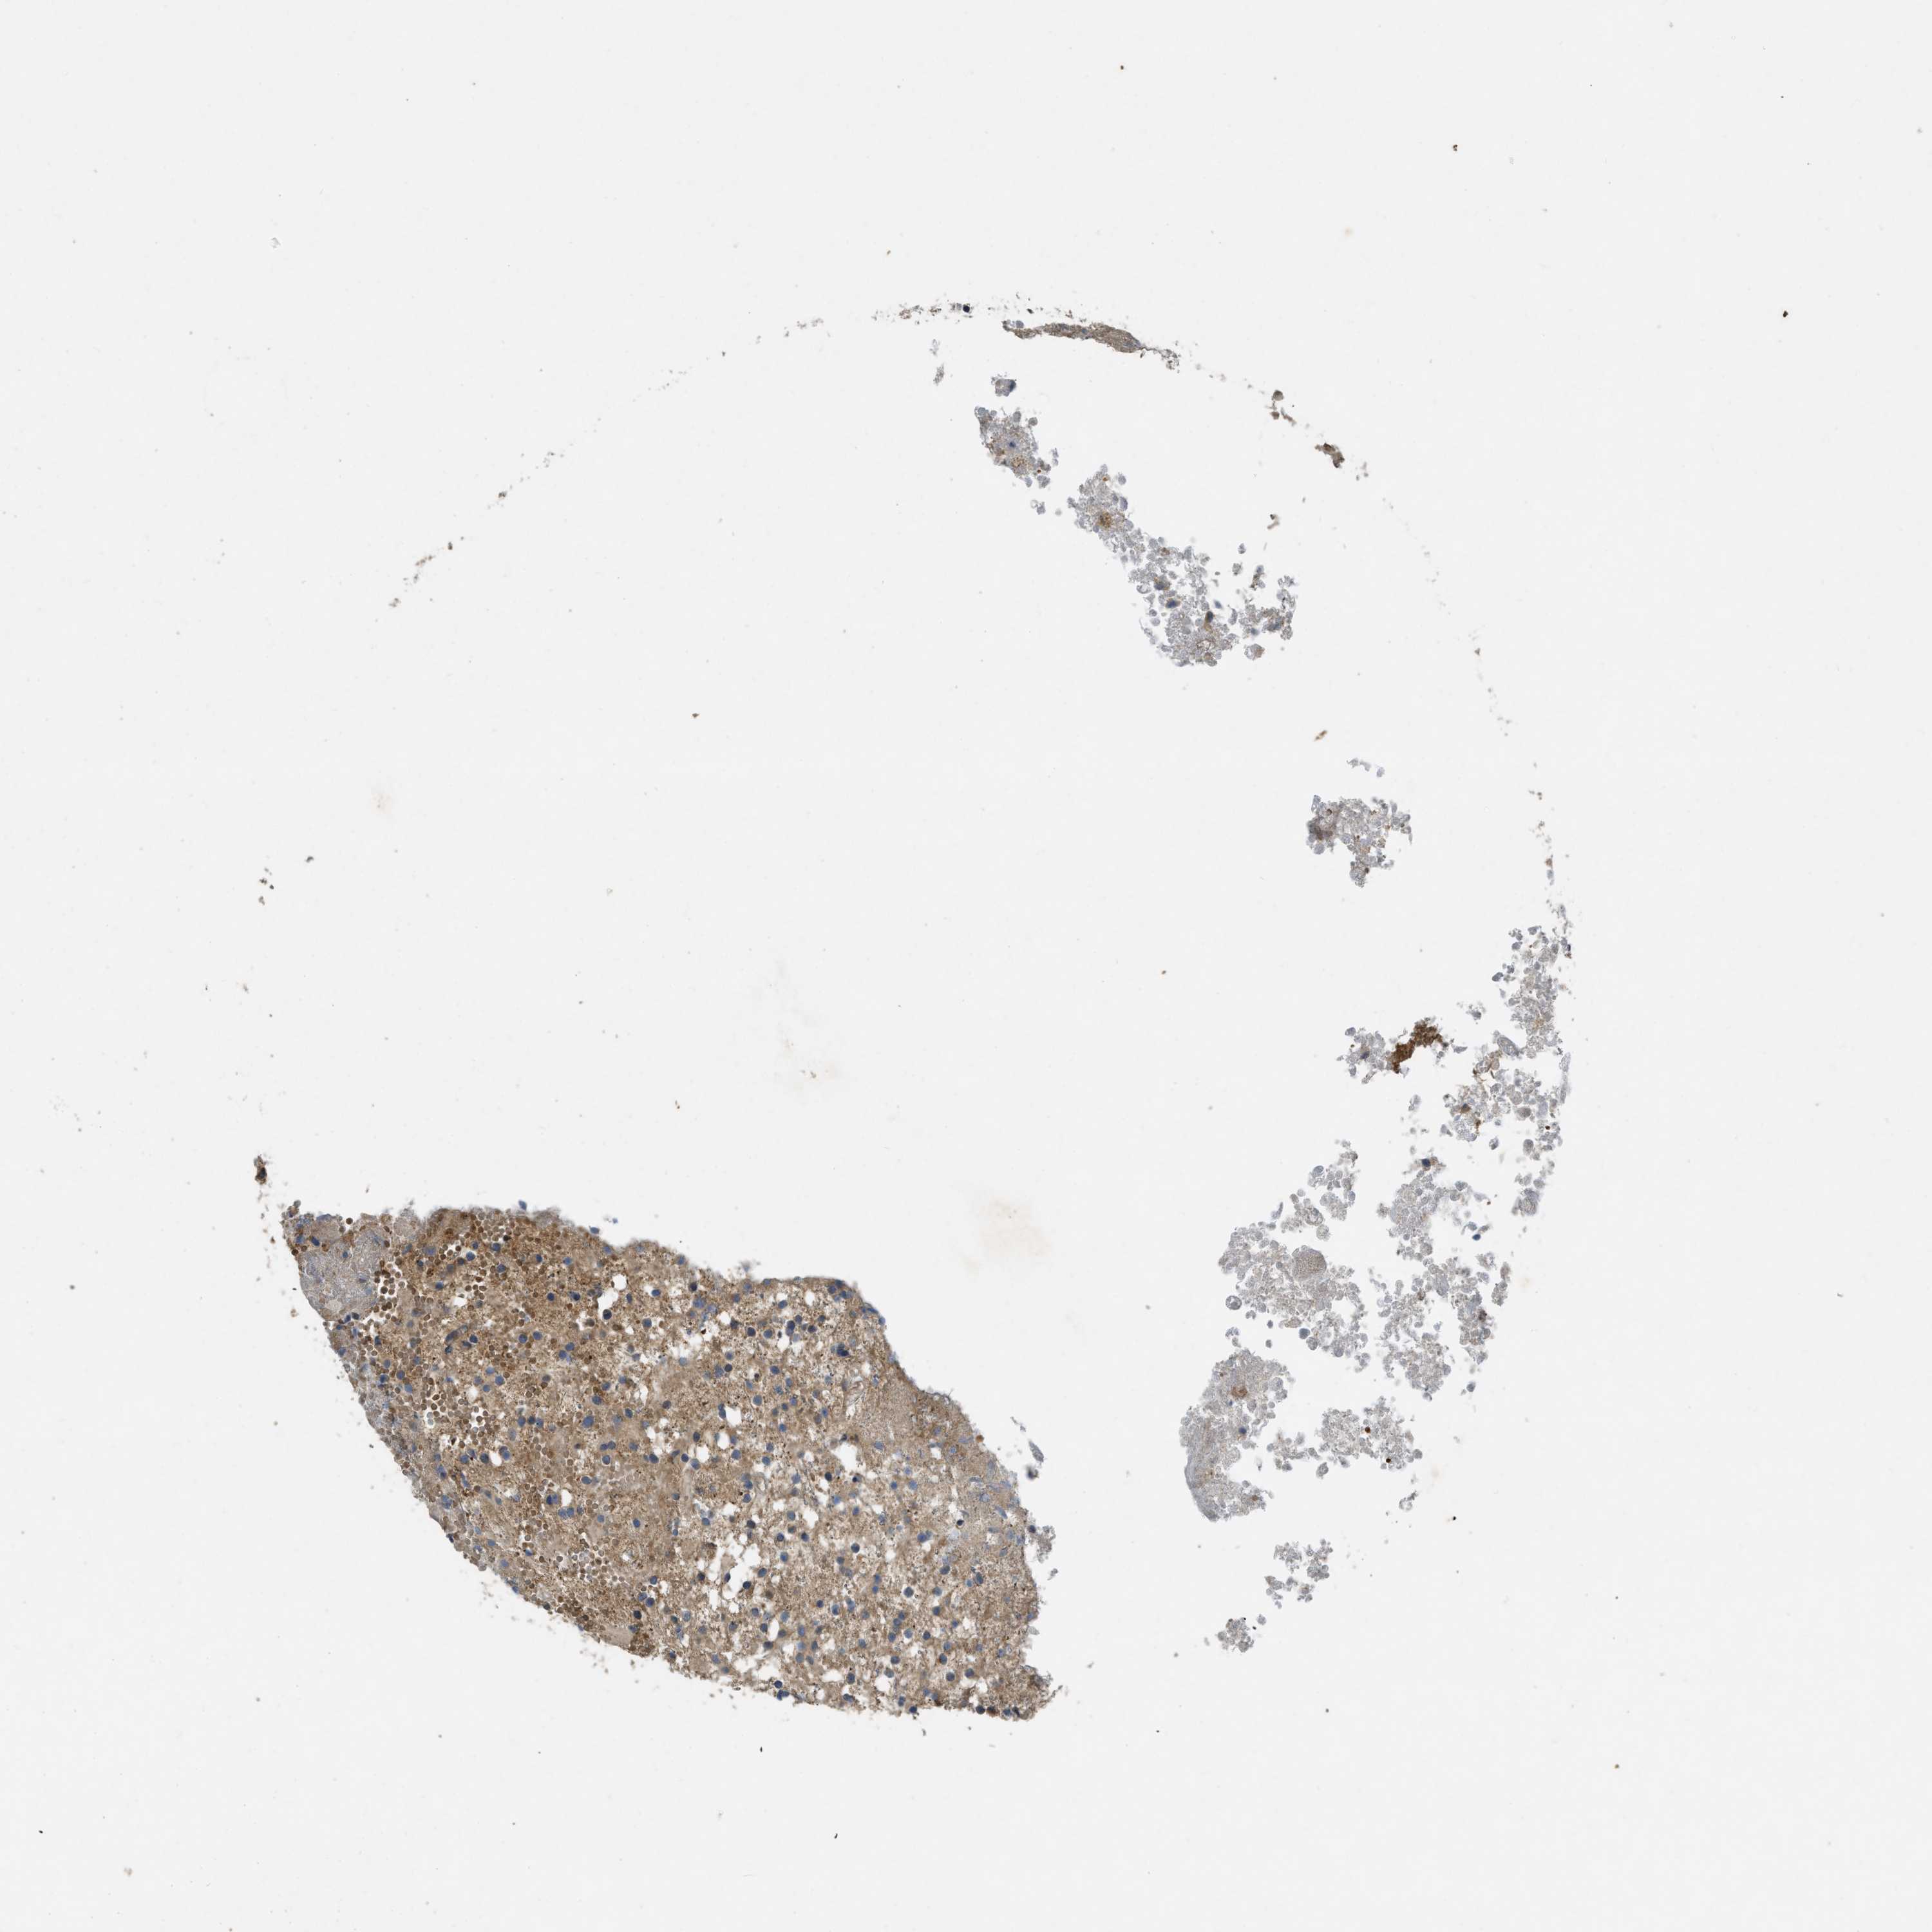

GLIOMA - Protein expressioni

A mouse-over function shows sample information and annotation data. Click on an image to view it in a full screen mode. Samples can be filtered based on level of antibody staining by selecting one or several of the following categories: high, medium, low and not detected. The assay and annotation is described here.

Note that samples used for immunohistochemistry by the Human Protein Atlas do not correspond to samples in the TCGA dataset.

Antibody stainingi

Antibody staining in the annotated cell types in the current human tissue is reported as not detected, low, medium, or high, based on conventional immunohistochemistry profiling in selected tissues. This score is based on the combination of the staining intensity and fraction of stained cells.

Each image is clickable and will lead to virtual microscopy that enables deeper exploration of all samples and also displays staining intensity scores, fraction scores and subcellular localization as well as patient and tissue information for each sample.

Antibody HPA012778

Antibody CAB018581

Staining

High

Medium

Low

Not detected

Intensity

Strong

Moderate

Weak

Negative

Quantity

>75%

75%-25%

<25%

None

Location

Nuclear

Cytoplasmic/membranous

Cytoplasmic/membranous,nuclear

Glioma, malignant, High grade

Glioma, malignant, Low grade